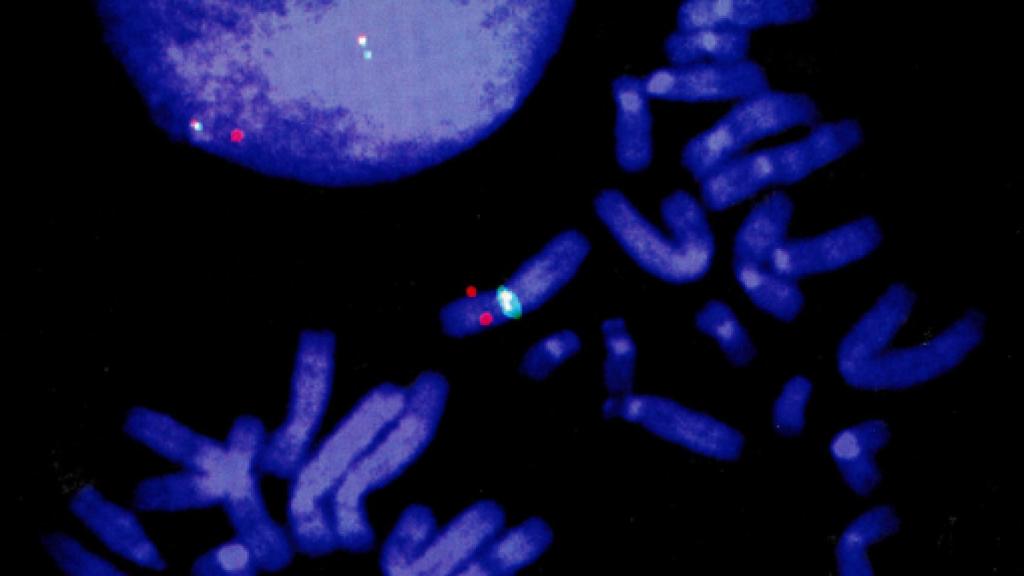

Cromosomas de célula humana. De Cielo y tierra (Phaidon)

Y finalmente está Cero K, una inquietante obra, al igual que otras de DeLillo, ésta girando en torno a la posibilidad de utilizar la criogenia (técnica que emplea temperaturas muy bajas, cercanas al límite de los cero grados Kelvin; de ahí el Cero K del título), junto a la nanotecnología, para conservar hibernadas personas a la espera de que llegue el día en que se conozcan las soluciones a su deterioro físico y puedan ser devueltas, ya sanas, a la vida. Ha coincidido mi lectura de este libro con la de Morir joven, a los 140 (Paidós), de la bióloga molecular Maria Blasco y la periodista Mónica Salomone, en el que se exponen las posibilidades de utilizar, para alargar la vida y combatir enfermedades que surgen frecuentemente con la edad, dos descubrimientos: el primero, que uno de los rasgos asociados al envejecimiento es el que al dividirse las células -y las de nuestros cuerpos lo hacen constantemente- los extremos protectores de cada cromosoma (los "átomos" de la herencia), unas estructuras formadas por ADN y proteínas llamadas telómeros, se acortan, hasta el punto de que tal acortamiento da una medida de la edad del individuo; el segundo descubrimiento es que existe una enzima, la telomerasa, que hace que vuelvan a crecer los telómeros. El problema es que nuestro cuerpo deja pronto de producir telomerasa y que suministrarla puede ser peligroso: los cánceres, no lo olvidemos, no son sino crecimiento imparable de células.